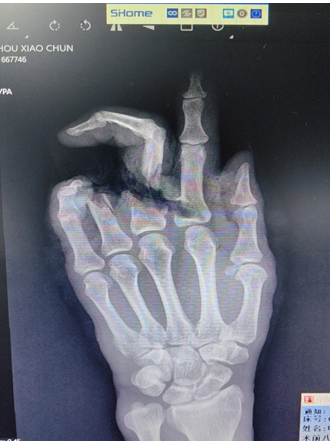

近日,广州市民周先生居家操作电锯时不慎将左手割伤,食指及中指仅小部分皮肤相连,拇指及小指掌侧也有横行切割伤口,顿时血流如注。

周先生伤情复杂,中指血管神经束为撕脱性离断,其中血管神经自近端完全撕脱抽出约2-3cm,骨折断端不整齐、骨缺损,肌腱断端回缩,让手术过程困难重重。

经过各种外科处理后,终于历时12小时,完成了3处指骨骨折的固定,9条屈指肌腱的修复;并在显微镜下完成5条动脉、6条静脉的吻合、1次前臂浅表静脉血管的移植修复,9条神经的修复,顺利完成了手术。